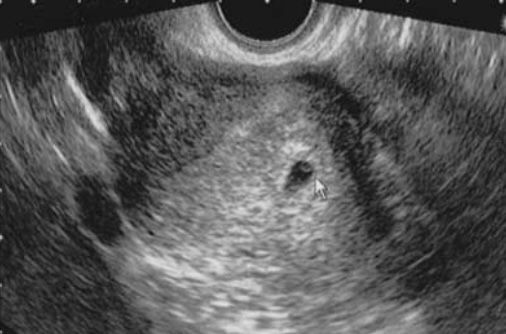

Сегодня сходила на узи (врач узист сказала что это или жидкость перед месечными или б)

Отправила своему гинекологу фото и протокол с узи сказала больше похоже на беременность

Скажите пожалуйста своим взглядом возможна ли это беременность 🙏🏻

Если тесты отрицательные откуда беременность? Если такая Б что видно аж на узи, то тесты должны гореть прям. По узи у вас нет желтого тела, это «железа» которая поддерживает беременность, если она состоялась. Задержка приличная, но это не беременность, к сожалению. Ждите м

сегодня приехала моя врач посмотрела меня и сказала что исключить беременность она не может т.к за 2 дня точка стала больше была 1.8 мм стала 2.4 мм

Ну по узи мб и Б , а может и нет (странно что жт нет).

Саша Жураp, зачем через 5 дней? Есди видно плодное яйцо, то хгч 1000+ уже.

Саша Жураp, да, по узи и был такой кругляш тоже. Но, честно, не верю в плодное яйцо и отрицательные тесты((( извините.